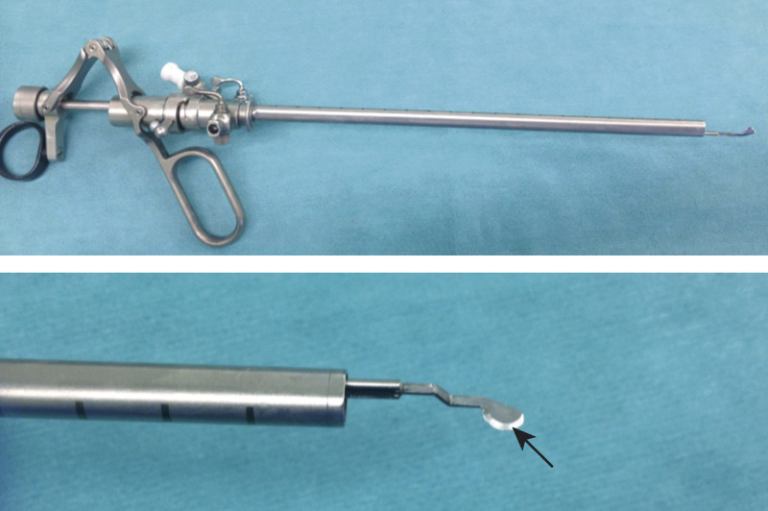

Nefroscopio

Telescopio Panoview con ocular desplazado lateralmente, dirección de visión de 12° y canal de trabajo de 6 Fr.

El nefroscopio minipercutáneo es recomendable para el tratamiento de piedras de 1 hasta 3 cm, tiene un canal de trabajo que permite el paso de instrumentos de hasta 6.7 french.

Su diseño compacto y la ventaja de realizar incisiones mas pequeñas permiten una recuperación mas rápida y la reducción de complicaciones postoperatorias.

Tras la incisión cutánea, se ensancha el acceso con un solo dilatador hasta el punto de que la vaina se pueda deslizar hasta el riñón, ya no es necesario recurrir a los dilatadores telescópicos o los dilatadores de varios tamaños.

La miniperc implica, además de la reducción del diámetro del tracto externo y del instrumento de trabajo (nefroscopio), otras modificaciones en la técnica de la litotricia en beneficio de la comodidad postoperatoria del paciente.

Entre estas modificaciones se encuentran el uso de tecnología láser para la fragmentación o pulverización de cálculos, la disminución de los elementos de extracción, la reducción del calibre de la nefrostomia (abertura desde el exterior del cuerpo hasta la pelvis renal) y diferente estrategia de salida.